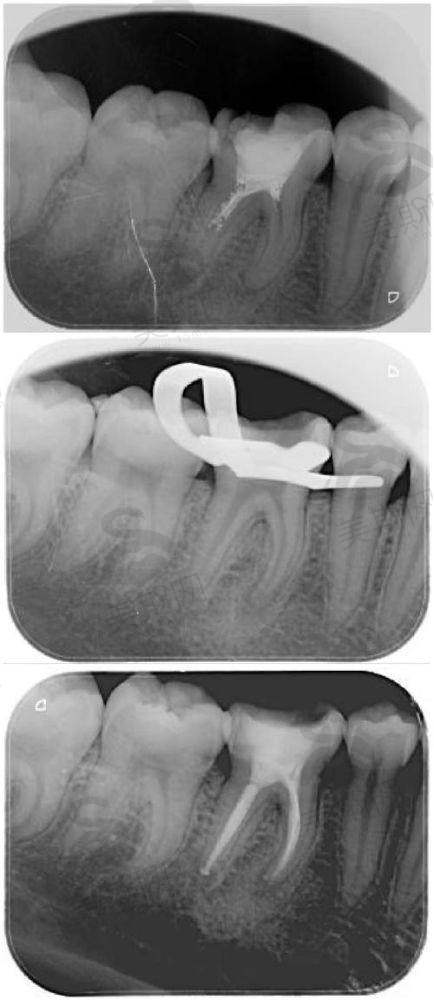

7. 综合齿科:涵盖补牙、拔牙、根管治疗、智齿拔除,采用微创拔牙技术,配合笑气镇静,减少术中痛苦,复杂根管治疗成功几率达98%。

技术流程上,首先通过德国卡瓦3D口腔CT对患者口腔进行全方面扫描,获取牙槽骨密度、骨量、神经血管分布等三维数据,精度达0.1mm;随后利用计算机种植导航系统模拟种植过程,设计至佳种植角度、深度和位置,生成可视化种植方案;接着采用3D打印技术制作个性化种植导板,确保种植体植入时精细定位;末尾通过微创技术(切口仅3 - 5mm)植入种植体,术中出血量少于5ml,术后无需缝合,实现“即拔即种、当天戴冠”。

技术优势显著:一是精细度高,种植误差控制在0.2mm以内,避免损伤神经和血管;二是创伤小,微创技术减少术后肿胀和疼痛,修复期从传统种植的3 - 6个月缩短至1 - 2个月;三是适用范围广,即使骨量不足的患者,也可通过数字化导板实现精细植骨,无需复杂植骨手术;四是成功几率高,累计完成3000余例种植病例,5年成功几率达98.5%,远超行业平均水平。该技术尤其适合单颗牙缺失、多颗牙缺失及全口无牙颌患者,已帮助2000余名患者重建口腔功能,重拾咀嚼自信。